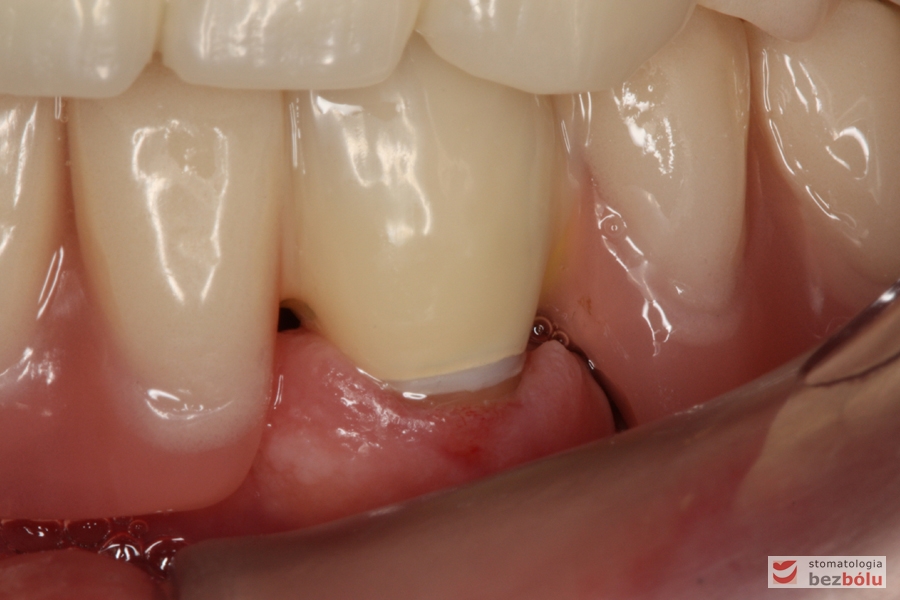

Gotowe patryce koron teleskopowych umieszczone w jamie ustnej na filarach zębów własnych